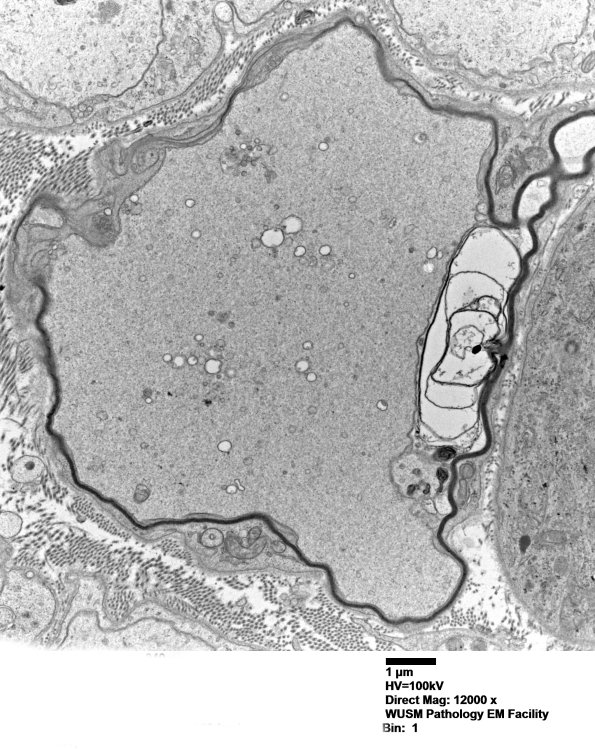

Washington University Experience | PERIPHERAL NEUROPATHY | 4 AXONAL DEGENERATION | 2 Plastic Sections | 12B5 W18-904A Irving E nerve_040 - Copy

Higher magnification of image #12B4.